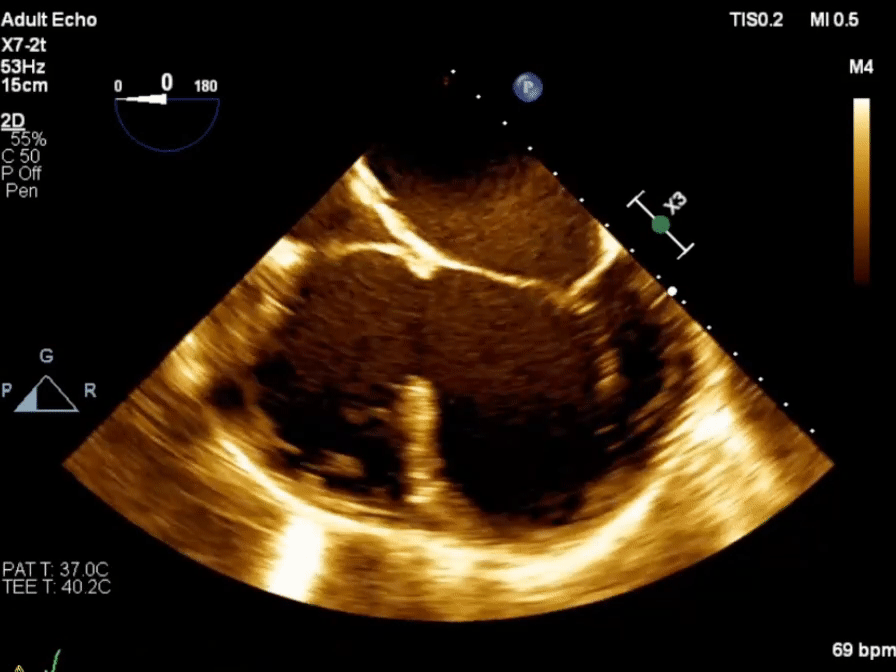

Echo in VSD

-1754871370645.webp)